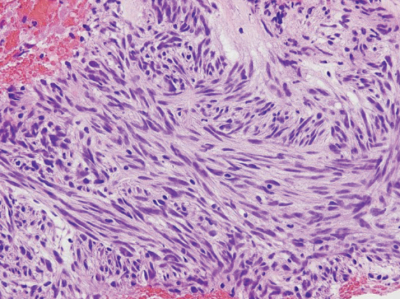

血液所見: 赤血球 399 万、Hb 11.5 g/dL、Ht 35 %、白血球 4,300、血小板 17 万。血液生化学所見:総蛋白 7.2 g/dL、アルブミン 4.1 g/dL、総ビリルビン 0.5 mg/dL、AST 20 U/L、ALT 16 U/L、LD 184 U/L(基準 120~245)、尿素窒素 21 mg/dL、クレアチニン 0.9 mg/dL、血糖 93 mg/dL。CRP 0.2 mg/dL。上部消化管内視鏡像と生検組織像(H-E 染色、KIT 免疫染色、α SMA〈平滑筋アクチン〉免疫染色を別に示す。腹部 CT で腫瘍径は 5.5 cm、他臓器への転移を認めなかった。

H-E染色像